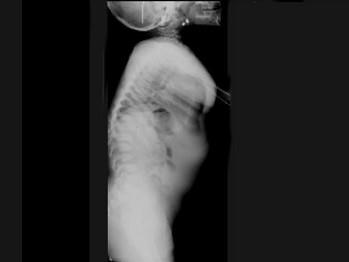

问题 女,3岁,身高不增,智力正常,请结合图像,选出最可能的诊断 ( )

选项 A、粘多糖贮积症I型 B、MPSII型 C、肾性骨病 D、粘多糖贮积症IV型 E、维生素D缺乏症

答案 D